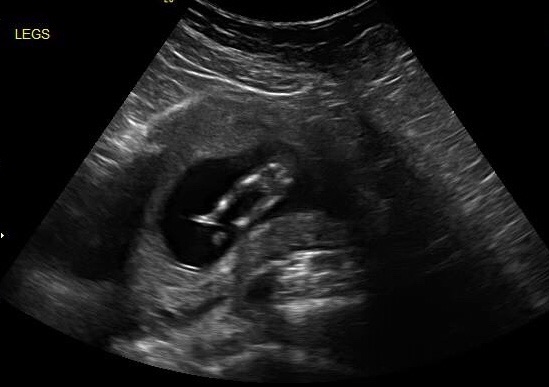

I had a scan today at 13 weeks, and I'm thinking girl but I'm afraid to get my hopes up. Anyone have any input??? TIA

Attachment 23674

Looks girly :)

I agree. Thinking pink!!

Looks girl to me!

Girly!

Pink

girly

Thanks so much!!! I have two sons (and a son I lost at 27 weeks), so I was pretty sure my husband only made boys. I'm so excited at the possibility of a girl!!!

So sorry for your loss:( This baby looks very girly.